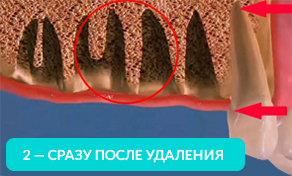

Отсутствие хотя бы одного зуба приводит к лавинообразной потери оставшихся.

Оставшиеся зубы начинают заполнять пустоты и смещаться.

На рисунке видно, какие щели между зубов образуются уже через год, после удаления.

Оставшиеся зубы смещаются в сторону и вытягиваются из десны. Зубам необходимо иметь опору (особенно при жевании). Если такой опоры нет, то они начинают ее искать и выдвигаться из десны.

Через год изменения уже будут видны невооруженным глазом. Выдвинутый зуб будет мешать при протезировании противоположного. Придется подпиливать выдвинувшийся зуб или возвращать его на место с помощью ортоимплантов.